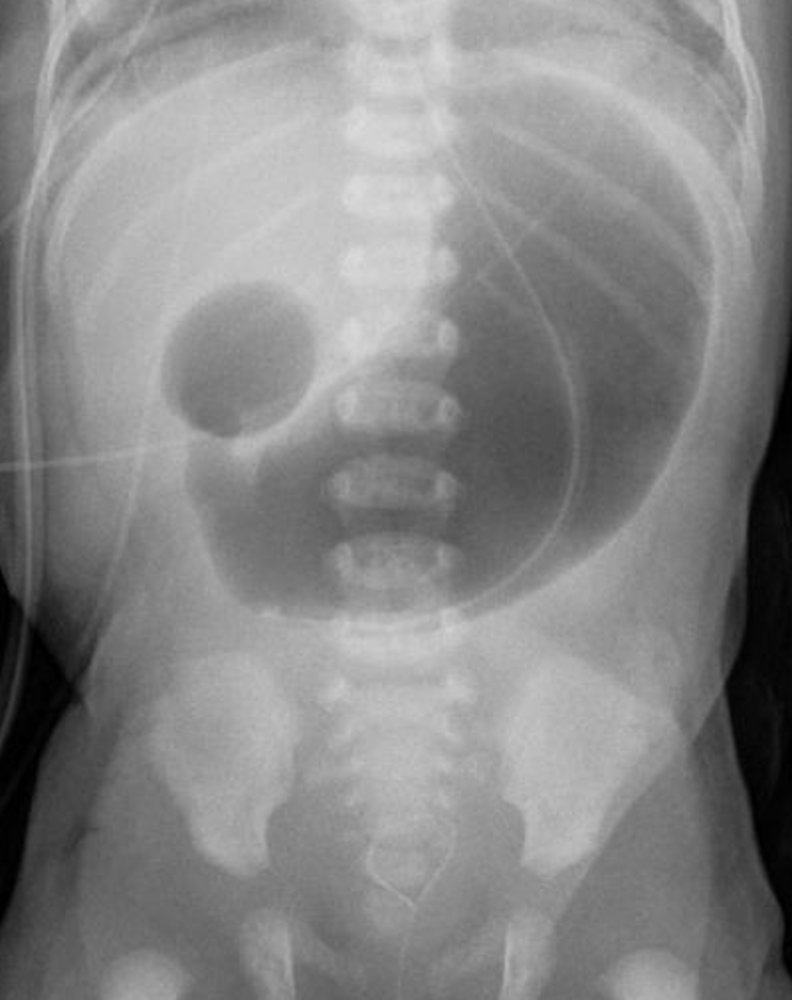

X-ray of the abdomen

Duodenal Atresia in a Newborn

(dilation of the pre-stenotic bowel segments (duodenum (D) and stomach (S)) with an air-fluid level in each dilated segment (double bubble sign). No air is visible in the post-stenotic bowel loops)